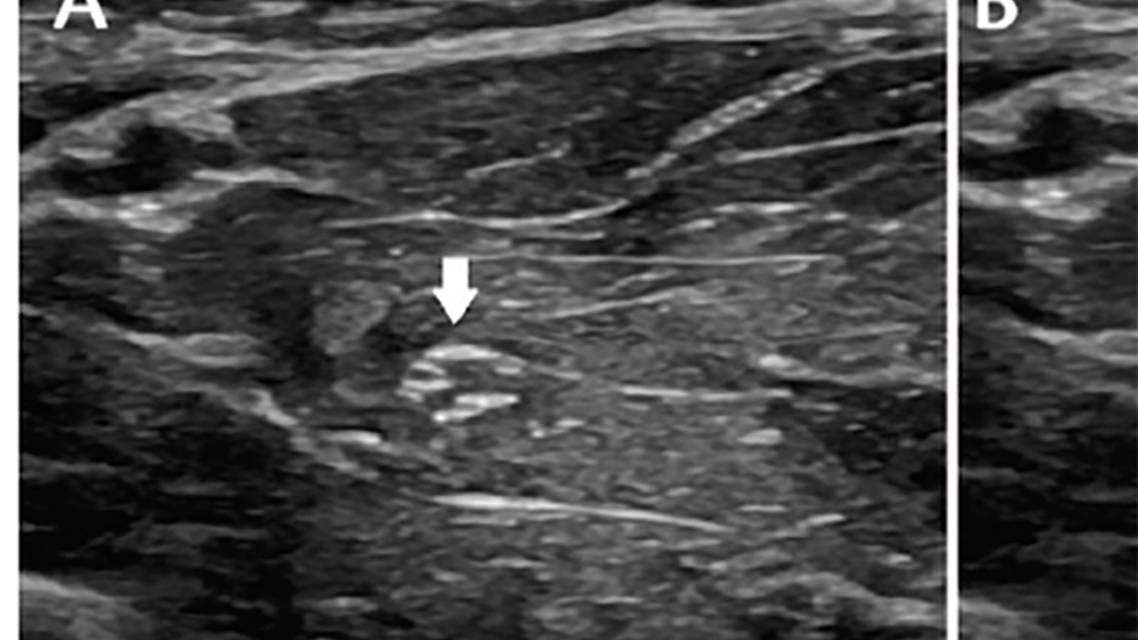

Scan the entire nerve, examining and documenting nerve size and variability, echogenicity, fascicle size, and nerve vascularity. Measure nerve enlargement as nerve cross-sectional area (CSA),8 by placing the transducer perpendicular to the nerve and tracing the nerve just within its hyperechoic epineurial rim (Figure 1).2 Nerve CSA remains relatively similar from the axilla to the wrist in the upper extremities, whereas the sciatic nerve CSA is more significantly reduced distally, owing to the splitting of the sciatic into the fibular and tibial nerves.2 Reference CSA values are available for most commonly studied nerves.9-11